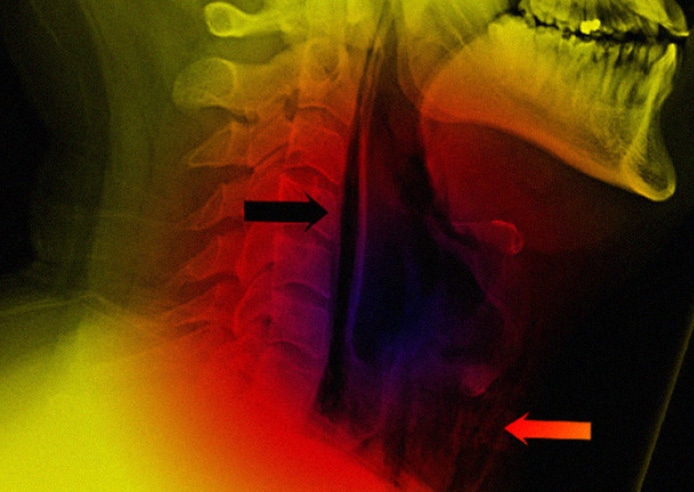

Британец пожаловался на острую боль при глотании и изменившийся голос, когда он плотно закрыл рот и зажал нос при чихании. Рентген показал сильную подкожную эмфизему перед трахеей, что свидетельствует о повреждениях легкого или воздухоносных путей, и скопление воздуха в носоглоточной области.

Позже врачи обнаружили значительное скопление воздуха в грудной полости и в шее от основания черепа до девятого грудного позвонка. Как оказалось, у мужчины произошел случайный разрыв стенки глотки.